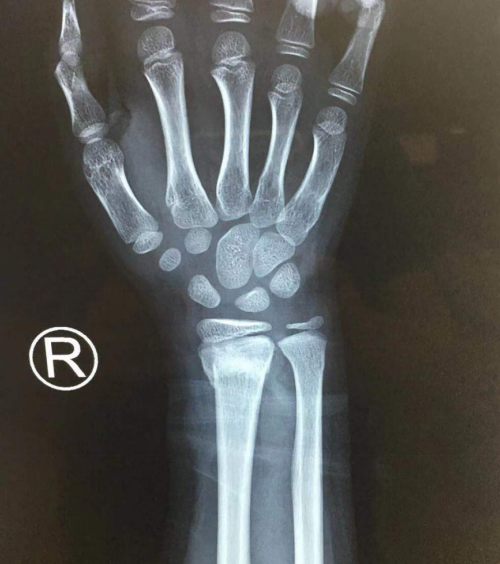

当天,手外科二病区熊祖国医师接诊后,检查孩子右腕呈“餐叉样”畸形,肿胀,压痛明显,腕部及各种自主活动受限。

经诊断,孩子桡骨远端伸直型骨折、尺骨远端骨折。跌倒时腕关节处于背伸及前臂旋前位、手掌着地,暴力集中于桡骨远端松质骨处而引起骨折。骨折远端向背侧及桡侧移位。

熊祖国手术小组立即为患儿实施急诊手术,术中在助手牵拉对抗下予以牵引复位桡骨远端骨折端,维持腕关节屈曲尺偏位,手法复查有桡骨远端骨折端及尺骨远段骨折端,2根克氏针于桡骨远端交叉打入固定,手术时间25分钟,微创方式完成右桡骨远端骨折闭合复位术。